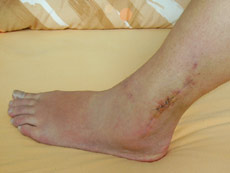

Für die nächsten sechs Wochen sind Rollstuhl und Krücken angesagt...